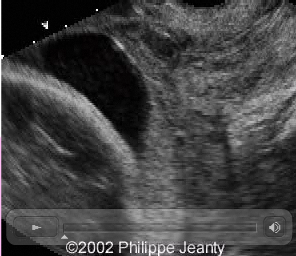

Source: www.thefetus.net

This is an artery with an interior velamentous insertion. Note on the greyscale there is no evidence of vasa praevia, but as the scan progresses to colour and the power doppler it is clear there is vasa praevia.

Again, there is no reason not to use colour doppler during these examinations. The diagnosis would have been missed otherwise.